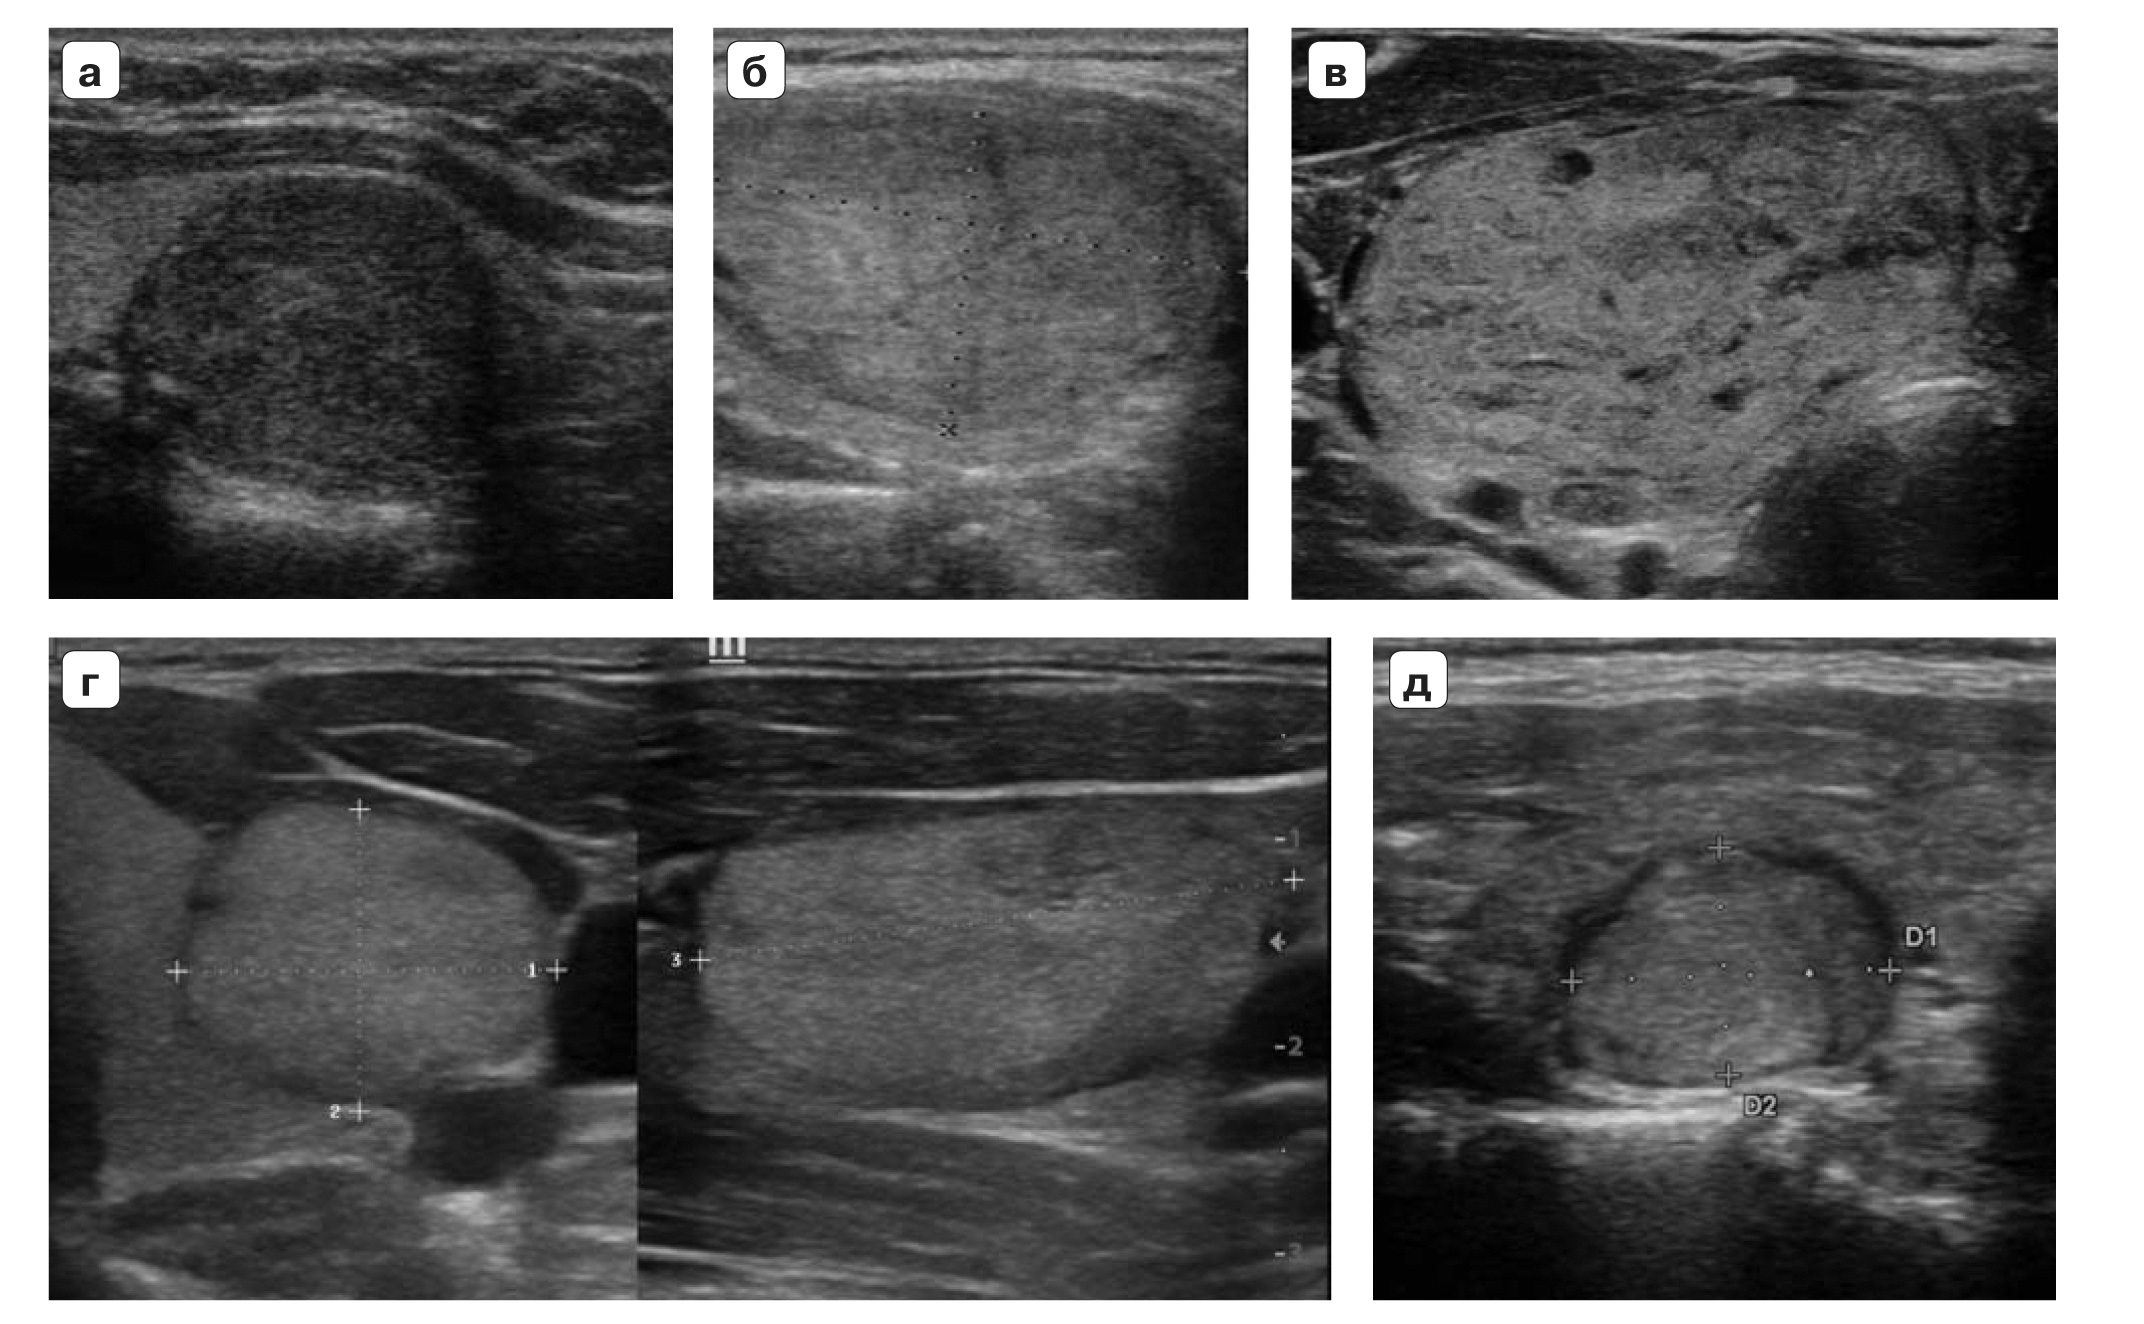

20. Fig. 5. TI-RADS 5. Thyroid nodes <1.0 cm in size: a - node with fuzzy and uneven radiant contours, vertical spatial orientation, significantly reduced echogenicity, with microcalcifications; b - a node of spherical shape, with fuzzy, blurry, uneven microlobular contours, moderately reduced echogenicity, with microcalcifications, grows to the thyroid capsule, deforming the external contour of the lobe. Cytologically and histologically in all presented nodes, papillary cancer was diagnosed.